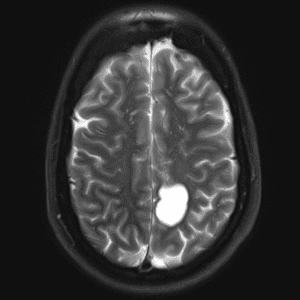

Case #14

CNS toxoplasmosis